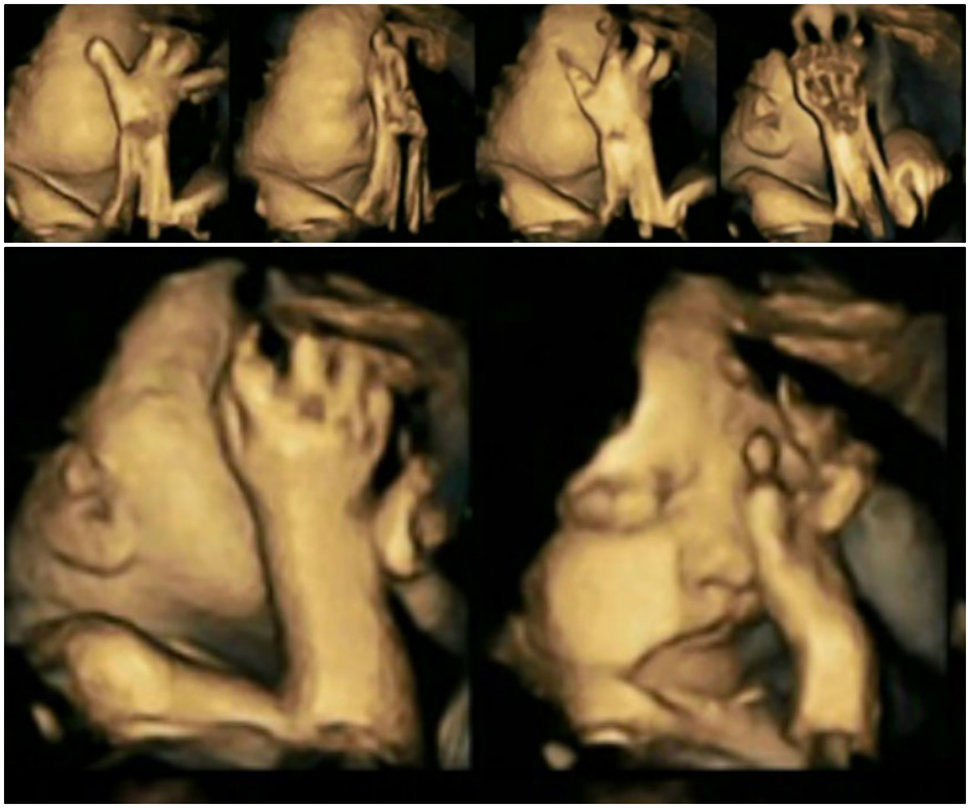

Aquí vemos un primer plano del feto expuesto al humo del cigarrillo. No somos científicos, pero nos parece seguro que está haciendo una mueca y frotándose los ojos. Algo así como lo que hacemos cuando alguien nos echa el humo de un cigarrillo en la cara.

Sin embargo, el feto de no fumadoras es así, como si durmiera una siesta. Como si no hubiera ninguna preocupación en el mundo.